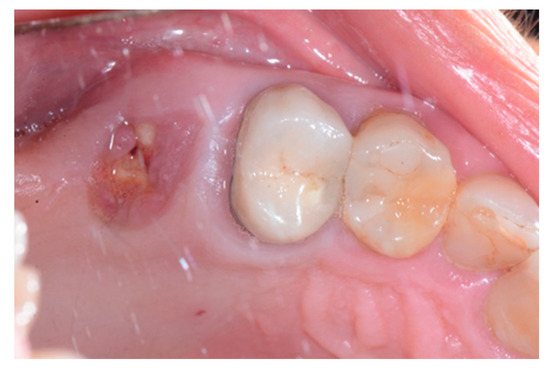

Figure 7.

Occlusal intraoperative view of the oral mucosa 10 days after tooth extraction and socket preservation. The exposed membrane was covered by a fibrin layer. Sound margins of the wound are visible.